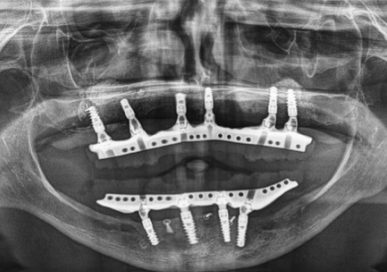

3. 서브페리오스테알 임플란트(Subperiosteal Implants)

치조골이 충분하지 않거나 치조골 이식을 원하지 않는 경우에 사용됩니다. 턱뼈 위에 직접 놓여지는 금속 프레임을 사용합니다.

✅ 설치 방법 : 잇몸 아래, 턱뼈 위에 금속 프레임을 배치하고 잇몸이 치유되면서 프레임이 고정됩니다.